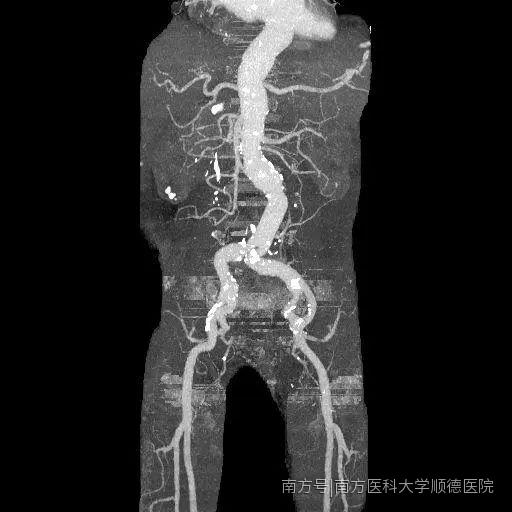

手術(shù)前CTA

所幸老郭的腹主動(dòng)脈瘤位置較低,位于腎動(dòng)脈水平以下。經(jīng)全院大會(huì)診,聯(lián)合心血管內(nèi)科、腎內(nèi)科、泌尿外科、麻醉科、手術(shù)室、體外循環(huán)等??疲槍?duì)老郭的病情,共同討論最適宜的手術(shù)方案,并制定出詳細(xì)、具體的治療方案。因主動(dòng)脈瘤近端與腎動(dòng)脈開(kāi)口距離較短,且瘤體直徑巨大,介入放置支架難以錨定,實(shí)施難度大,最終決定選擇腹主動(dòng)脈瘤切除和人工血管置換手術(shù)治療。